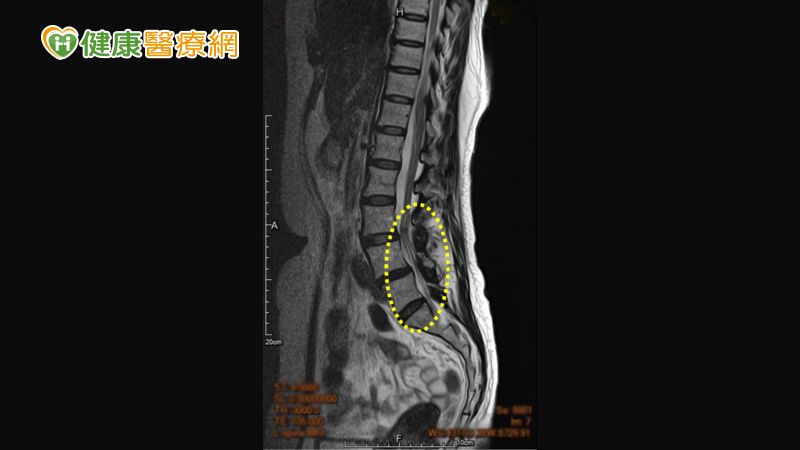

因無法久坐久站、座立難安,造成生活及工作上的困擾,轉至醫院求診進行X光及核磁共振MRI檢查,發現其腰椎退化,診斷為腰椎第三與第四節椎孔嚴重狹窄、腰椎第四與第五節輕度滑脫,造成坐骨神經痛;由於陳小姐希望保守治療盡量不開刀,醫師遂採脊椎硬膜上注射治療並搭配每日復健運動,調整不良座姿減少久坐,所幸經三個月治療,疼痛症狀已大幅改善。

椎孔是脊髓及神經的管道,腰椎狹窄是脊椎結構退化、進而壓迫到神經,出現痠麻刺痛 ▲椎孔是脊髓及神經的管道,腰椎狹窄是脊椎結構退化、進而壓迫到神經,出現痠麻刺痛

西園醫院復健科徐伯誠主任表示:『椎孔是脊髓及神經的管道,「脊椎狹窄(或稱椎孔狹窄)」指的是脊椎結構退化、進而壓迫到神經。』骨骼約在30歲後逐漸顯現退化,吸菸、過重、搬重物、有背痛病史、久站久坐、缺乏運動、常彎腰者,會加速退化情況。腰椎的退化包括椎間盤、小面關節、韌帶等結構,若退化到椎骨不穩定導致椎間盤突出、黃韌帶增厚、腰椎滑脫,進而造成神經的壓迫,下肢會出現痠麻刺痛、灼熱感等坐骨神經痛症狀;嚴重的話,還可能造成下肢無力、大小便失禁,必須立刻處理。